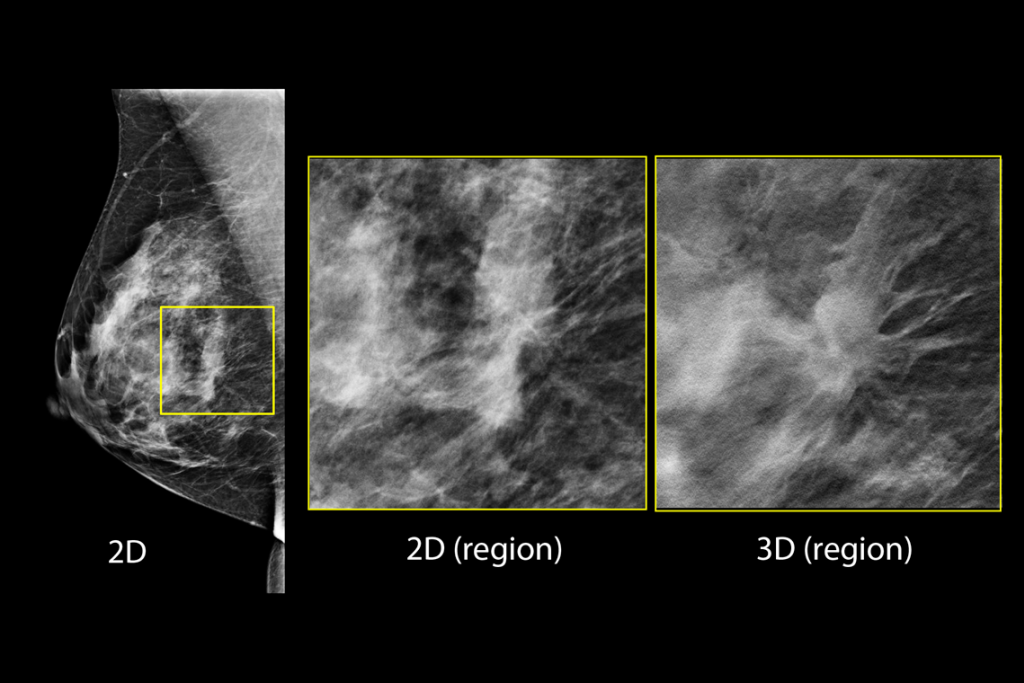

The Selenia Dimensions system delivers proven accuracy of our 3D Mammography exam to detect significantly more invasive breast cancers earlier and reduce call backs vs 2D alone.2-6,*

Detects up to 65% more invasive breast cancer, and reduces recalls by up to 40%, compared to 2D alone.2-4,*

Superior Accuracy

Superior accuracy for women with dense breasts compared to 2D alone.6

Clinical Images